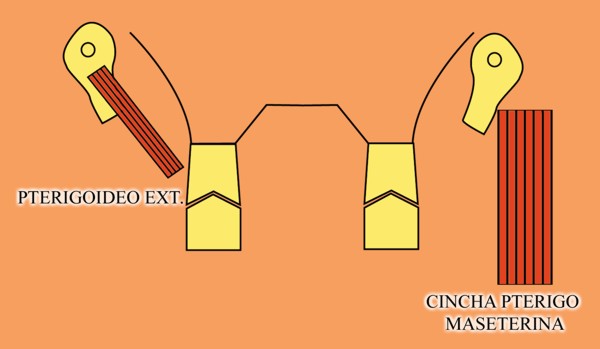

RESUMEN Más allá en el tiempo, respecto de las razones más frecuentes de fracasos como temperatura de fresado, infecciones, falta de fijación inicial, falta de higiene, etc., la OCLUSIÓN recibe sobre sí, la responsabilidad de la permanencia de la osteointegración, como así de la ortofunción del sistema todo. Sometimes ago,conserning the most frecuent reason of failures such as the strawberry action temperature, infections and lack of hygiene…etc.,the OCLUSION has itself the responsability af having the osteointegration well as the allsistem ortofunction . DESARROLLO La valoración de los fracasos en IMPLANTOLOGÍA es difícil de contabilizar sobre todo después del año, ya que el confort logrado por lo general, hace que el paciente realice correctamente sus primeros controles, y después; apoyado en su bienestar; intente subconscientemente olvidar ese período de su vida, que si bien le devolvió su capacidad masticatoria, fonética, social, etc., le ocasionara gastos, molestias, sufrimientos. … la APLICACIÓN de dichas fuerzas, requiere de una exactitud mucho mayor. Los esquemas propuestos a través de los años, no son muchos ni muy variados… I-Evitar las fuerzas tangenciales. II-Repartir las fuerzas lo máximo posible. Sin embargo, muchas veces se confunden los conceptos anteriores con criterios inexactos. Por ej: a-Reducción de las caras vestibulares y palatinas, aceptando que la menor superficie de intercontactos reduce la carga. b-Utilización de la Función de Grupo Posterior, en la creencia de que repartiendo el esfuerzo en las piezas posteriores, ganamos resistencia; a la potencia ejercida por los músculos. c-No permitiendo el contacto excéntrico de un canino implantado, para aliviarlo de las cargas laterales, sobre cargando de esta manera la tabla premolar-molar en el Lado de Trabajo. Algunos conceptos aislados, que forman parte de toda una filosofía de la Oclusión (OCLUSIÓN ORGÁNICA), sean tal vez de ayuda para echar luz sobre los preceptos anteriores. 1º-PROPORCIONES FUNCIONALES DE UN PAR OCLUSAL En la figura siguiente, observamos la relación final masticatoria de un PAR OCLUSAL: En el se ven los contactos puntiformes, producto del choque de superficies redondeadas contra superficies redondeadas («Solo pueden encontrarse en un punto» Ref: Principios Mecánicos Esferoidales.W.Mc.Horris.) Si Miramos con atención este tipo de contactos interoclusales, veremos que la superficie actuante es mucho menor que la superficie total de la cara oclusal: 45% (Fig.1) Por lo tanto, si no es por razones del Pilar de Emergencia para no crear un espacio biológico inadecuado… ¿POR QUÉ REDUCIR LA CARA OCLUSAL VESTÍBULO LINGUALMENTE? (Figs. 2-3-4-5) Si observamos con atención las figuras 2-3-4-5, veremos desde todos los planos , que el área contactante es muy reducida respecto del ancho oclusal total, siendo las fuerzas resultantes , AXIALES al eje implantario. 2º-FUNCIÓN DE GRUPO POSTERIOR. FUNCIÓN CANINA. Tres son las razones por las cuales nos inclinamos a la utilización de la Función Canina. En cambio, en el esquema de FUNCIÓN CANINA, podemos observar que el BRAZO DE POTENCIA, es prácticamente igual al de RESISTENCIA, equilibrando de esta manera la palanca y destruyendo mucho menos las estructuras de soporte(Interface I-H) (Fig. 7) Otra de las razones de peso en este tema es la DIFERENCIA DE ANGULACIÓN que existe entre la cara palatina del canino y las vertientes contactantes del sector premolar-molar. A MAYOR ANGULACIÓN, MENORES FUERZAS LATERALES(Perpendiculares al Plano), y por lo tanto , menor destrucción de la interface Hueso-Implante(Figs. 9-11). DIFERENCIAS EXCITATORIAS DE LOS GRUPOS MUSCULARES. Por último debemos considerar que el intercontacto dentario del sector anterior, estimula excitatoriamente a las fibras anteriores y verticales del temporal (Figs.12-13-14-15), mientras que los contactos posteriores lo hacen con la cincha pterigo-maseterina(Fig. 16-17-18-19) Por lo tanto ,si se comprende el fisiologismo de estos conceptos, es sencillo entender que la sobrecarga de los sectores posteriores es nocivo generando fuerzas tangenciales de Alto Potencial Patológico. 3º-FUNCIÓN DE GRUPO ANTERIOR Las ventajas de un Brazo de Resistencia mayor se acentúan cuando tenemos el esquema de FUNCIÓN DE GRUPO ANTERIOR. Además, debemos tener en cuenta que, durante la función de un Ciclo Masticatorio, es más importante la Desoclusión Final que la Desoclusión Inicial, ya que al ser más larga esta última, es durante el transcurso de su deslizamiento cuando se ejercen fuerzas laterales mayores(Fig. 21) A medida que la punta del canino inferior se acerca a la O.R.C., o sea al Punto de Contacto Intercanino, las fuerzas laterales disminuyen en virtud del acortamiento del brazo de potencia de la palanca, hasta que, al terminar su recorrido, la fuerza es proyectada axialmente sobre el eje del canino superior, debido a que, al margen de la intensidad que la fuerza trae durante el cierre, la dirección de la misma «apunta» en esa dirección. Por eso decimos que los caninos Axializan el Ciclo Masticatorio. Si estamos imitando en lo posible a la naturaleza, no olvidemos este detalle que los dientes naturales provéen, para evitar las fuerzas laterales del canino a la hora de realizar la supraestructura coronaria del mismo. Es ahora menester acentuar que la problemática concreta se manifiesta, no durante la función, sino durante la PARAFUNCIÓN… Cuando estudiamos recorridos de la Dinámica Mandibular, desde el conocido Bicuspoide de Posselt hasta cualquiera de los registros pantográficos, estamos invirtiendo la dirección del movimiento… A.- El primer premolar es el más anterior de la tabla oclusal posterior. Por lo tanto el brazo de resistencia es el mayor de dicha tabla. B.- El lateral, como parte del grupo anterior, cuenta con un empotramiento tipo «clavo largo», y el interseptum lateral -canino, que se opone a la fuerza, es mucho más grueso que la tabla vestibular del primer premolar(Fig.23) C.- Condiciones, las dos anteriores que se favorecen considerablemente, si al enfundar el lateral se logra junto al central una Función de Grupo Anterior. D.- De manera más artificiosa, la instalación de una placa de relajación, soluciona durante la noche lo nocivo de las fuerzas laterales. Veamos un par de casos, como ejemplo de lo dicho: Paciente de 54 años que se presenta a la consulta portando prótesis completa superior y antagonista natural que soporta fundas de porcelana. Obsérvese la función de grupo posterior ejercida, y las consecuencias de la misma: Otro paciente que presenta fractura de la cúspide fundamental de un onlay de porcelana antagonista de cinco piezas implantadas (Fig.27). Radiográficamente se observa la desinserción de uno de sus abuttments cementados (Fig.28). En el Lado de Trabajo (LT), no existe el canino encargado de desocluir la zona afectada (Figs.29-30) Como corolario, cabe entonces una pregunta: ¿Es el Implante en el canino quien debe preservar de patología oclusal al resto del sistema…. ¿Es el Implante…un medio…o un fín? BIBLIOGRAFÍA 1- Dibujos tomados del libro del mismo autor: «OCLUSIÓN ORGÁNICA… UN CAMINO HACIA LA REHABILITACIÓN ORAL»(en preparación) 2- «NEUROFISIOLOGÍA DE LA OCLUSIÓN» 3- «OCLUSIÓN Y FUNCIÓN» 4- «FUNDAMENTOS, TÉCNICAS Y CLÍNICA EN REHABILITACIÓN BUCAL» 5- «OCLUSIÓN Y REHABILITACIÓN» 6- «DISFUNCIÓN TEMPOROMANDIBULAR» 7- «PROCEDIMIENTOS CLÍNICOS Y DE LABORATORIO DE OCLUSIÓN ORGÁNICA» 8- «ESTUDIO ELECTRÓNICO DEL MOVIMIENTO MANDIBULAR» 9- «OCLUSIÓN: CONCEPTO PARA EL CLÍNICO» 10- «IMPLANTOLOGÍA CONTEMPORÁNEA» 11- «OCLUSIÓN Y DIAGNÓSTICO EN REHABILITACIÓN ORAL» 12- «PRINCIPIOS DE OCLUSIÓN»

Sabemos que la fuerza desarrollada por el Pterigoideo Int. y el Masetero, músculos elevadores por excelencia, manifiestan durante el acto masticatorio su máxima expresión(LT), por lo tanto es evidente que dichas fuerzas soportadas fuera del eje axial de la pieza ,determinan grandes daños para las estructuras de soporte.